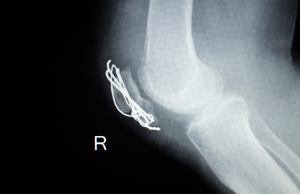

- Imaging Studies: X-rays or CT scans evaluate implant placement and bone healing.

- Knee: Screws from fracture repair surgeries can sometimes cause discomfort or prominence.